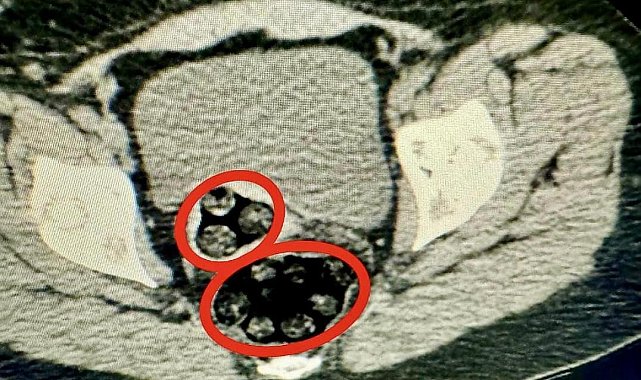

Uyuşturucu kuryesi İranlı kadının makadından 94 parça halinde toplam 550,63 gram uyuşturucu çıktı. Uyuşturucu kuryeliği yapan kadın tutuklandı.Kars il Emniyet Müdürlüğü Narkotik Suçlarla Mücadele Şube Müdürlüğü uluslararası uyuşturucu madde kuryeliği yapan Fahımeh Golmohammadı Yenkejeh'in Kars'a geleceği yönünde bilgi aldı. Bunun üzerine harekete geçen narkotik ekipleri Fahımeh Golmohammadı Yenkejeh'in de içerisinde yolcu olarak bulunduğu ve Iğdır-Trabzon seferini yapan otobüse operasyon düzenledi.94 parça uyuşturucu cerrahi müdahale ile çıkarıldıOtobüste gözaltına Fahımeh Golmohammadı Yenkejeh'in yapılan iç beden muayenesinde makadında cisim olduğu tespit edildi. Fahımeh Golmohammadı Yenkejeh'in makadına saklanmış bir şekilde 94 parça 550,63 gram metamfetamin uyuşturucu maddesi cerrahi müdahaleyle çıkarıldı.Gözaltına alınan Fahımeh Golmohammadı Yenkejeh, İl Emniyet Müdürlüğü'ne getirildi. Burada işlemleri tamamlanan şüpheli, çıkarıldığı mahkemece tutuklanarak cezaevine gönderildi.